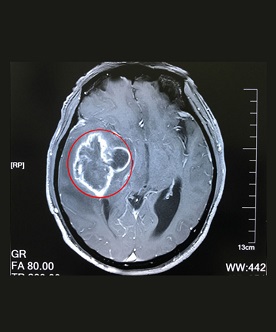

腦膠質(zhì)瘤是由于大腦和脊髓膠質(zhì)細(xì)胞癌變所產(chǎn)生的、常見的原發(fā)性顱腦腫瘤,年發(fā)病率約為3-8人/10萬人口。如同其他腫瘤(疾。┮粯,膠質(zhì)瘤也是由于先天的遺傳高危因素和環(huán)境的致癌因素相互作用所導(dǎo)致的。腦膠質(zhì)瘤以頭痛、嘔吐、視力減退、復(fù)視、精神癥狀、神經(jīng)功能缺失等為主要癥狀表現(xiàn)。

在確診腦膠質(zhì)瘤時(shí),一定要做的必然是檢查。那,腦膠質(zhì)瘤需要做哪些檢查?上海藍(lán)十字腦科醫(yī)院專家解析:膠質(zhì)瘤(gliomas)是發(fā)生...【詳細(xì)】